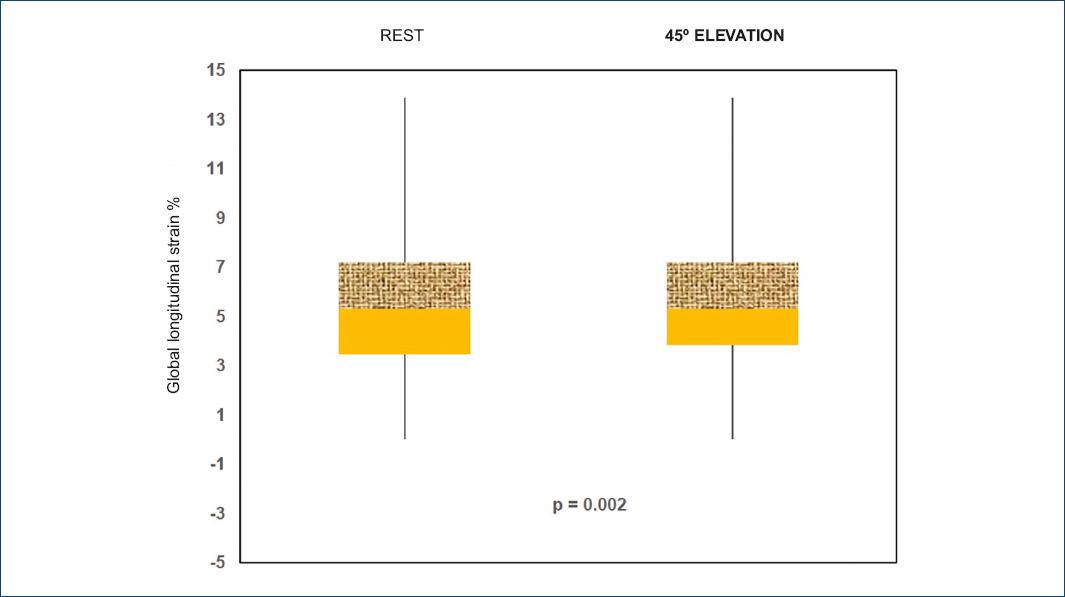

Thirty-one subjects were analyzed, 16 men and 15 women with ages ranging from 16 to 53 years. GLS and SLS behavior before and after leg elevation to 45° is shown in table 1 and figure 1; a box and whisker plot shows mean differences and the distribution is observed to be larger (i.e., higher dispersion), and there is also a positive bias for the subjects at rest (Fig. 2). The intra-class correlation coefficient was calculated: 0.773, with a 95% confidence interval (CI) of 0.534-0.890; p < 0.001.

| GLS | —23.06 ± 3.4 | —24.5 ± 2.9 | 0.002 |

2D STE measures RV GLS and SLS with a four-chamber approach. We measured it in healthy subjects at rest and with position changes (leg elevation to 45°), a maneuver that was used with the purpose to increase preload. There are no previous studies on RV performing this maneuver. There are studies on LV where STE-observed longitudinal and circumferential strain has been calculated to be affected by acute changes in saline infusion-induced preload16. We obtained significant GLS and SLS differences in the basal and mid-RV free-wall segment. We found that the strain is more negative with leg elevation to 45°, which supports that the greater the stretching of the myocardial fiber by increasing the preload, the more negative the generated deformation, indicating that there is a greater shortening of the fiber, and this method can measure those differences.